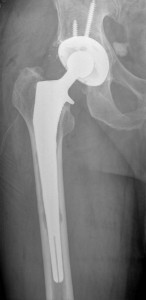

The past decade has witnessed an exponential increase in the number of people replacing their damaged hips or knees. With such developments, a number of failures have been reported. The popularity and demand for these surgeries have increased something that has also seen a sharp increase in the number of complaints reported. From the number of recalls DePuy recorded in 2006, thousands of patients have continued to file lawsuits claiming the medical devices are highly defective. The following things are worth noting.

In recent years, several articles have been published about failed hip and knee replacement procedures and their surrounding medical lawsuits. This has caused an understandable reaction of uncertainty and anxiety among thousands of patients in Savannah; GA and nationwide. DePuy’s highly marketed ASR implant was the center of this controversy.

The implant failed to a greater percentage resulting from design issues that have been uncovered and proven in multiple scientific and research articles. Despite the early warning signs, DePuy continued to market the implant as late as 2006. Due to piling pressure, DePuy eventually pulled it down in 2010 only after the story was continuously published in the New York Times.

After several lawsuits, DePuy agreed to cater to the revision surgery on any patient with a failed implant due to design flaws.